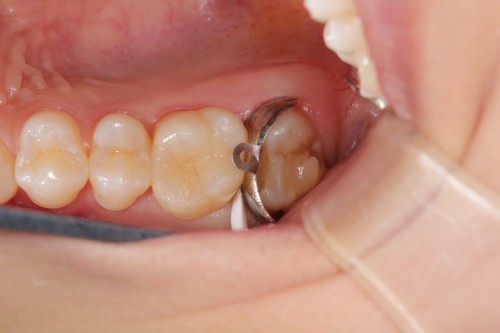

前歯の虫歯です。唾液の量が多い方や歯ぐきから出血がある方にはラバーダム防湿法を使います。このように緑色のゴムのシートを使用して、歯に唾液や血液が付かない様にします。

虫歯をとったところです。

無事治療が終わりました。削った穴に唾液や血液が入り込むと接着力が低下してしまいます。今回、削った穴に汚れが付く事無く、審美的な治療が出来ました。

ダイレクトボンディング

費用2万円×2本

リスクとして変色や欠ける可能性がある(修復可能)。